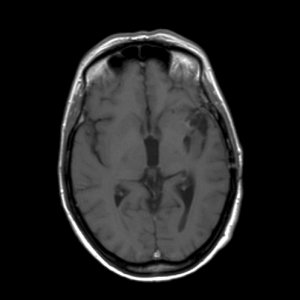

Een astrocytoom graad III groeit onbehandeld snel door in het omliggende hersenweefsel; de ziektegeschiedenis is daarom meestal relatief kort. De meeste patiënten zijn tussen de 30 en 50 jaar oud, iets vaker mannen dan vrouwen. Een MRI toont meestal een grillige, slecht begrensde tumor die met contrast kan aankleuren. De diagnose moet gesteld worden door onderzoek van het weefsel.

'Hoe is het mogelijk, dit kan niet, dit is bizar, zoiets heb ik nog nooit gezien maar het is waar'. Dit waren de woorden van de neuro-oncoloog. Mijn vriendin Ineke en ik bogen ons naar haar computer waar het onverklaarbare resultaat stond. Op de MRI-scan was te zien dat de kwaadaardige tumor zich had teruggetrokken. De tumor had een donkere holte met een grillige tumorrand achtergelaten. De neuro-oncoloog benadrukte nog eens dat het echt heel bijzonder was en dat zij en de radioloog voor een raadsel stonden. Ik vroeg haar wat dit betekende voor de prognose van mijn levensverwachting. Ze zei dat er nog één of misschien zelfs twee jaar zou bijkomen. Meer durfde ze er ook niet over te zeggen.

De MRI-scan van oktober 2009

De MRI scans van 2006 en 2007 zijn niet correct geïnterpreteerd. Wat toen als tumorgroei werd gezien blijkt nu een reactie van de bestraling te zijn. De chemokuur was overbodig omdat de tumor niet groeide. Wat je nu ziet is de tumor die enigzins gegroeid lijkt, maar dat is niet zeker. Als het zeker is moet je overwegen om opnieuw bestraald te worden. Meer patienten zijn ook met de verkeerde boodschap (dat de tumor groeit) naar huis gegaan,ook in andere ziekenhuizen.